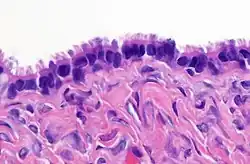

High magnification micrograph of a Brenner tumor, a type of surface epithelial-stromal tumor. H&E stain. | |

Brenner tumor

Brenner tumors are uncommon surface-epithelial stromal cell tumors in which the epithelial cell (which defines these tumors) is a transitional cell. These are similar in appearance to bladder epithelia. The tumors may be very small to very large, and may be solid or cystic. Histologically, the tumor consists of nests of the aforementioned transitional cells within surrounding tissue that resembles normal ovary. Brenner tumors may be benign or malignant, depending on whether the tumor cells invade the surrounding tissue.